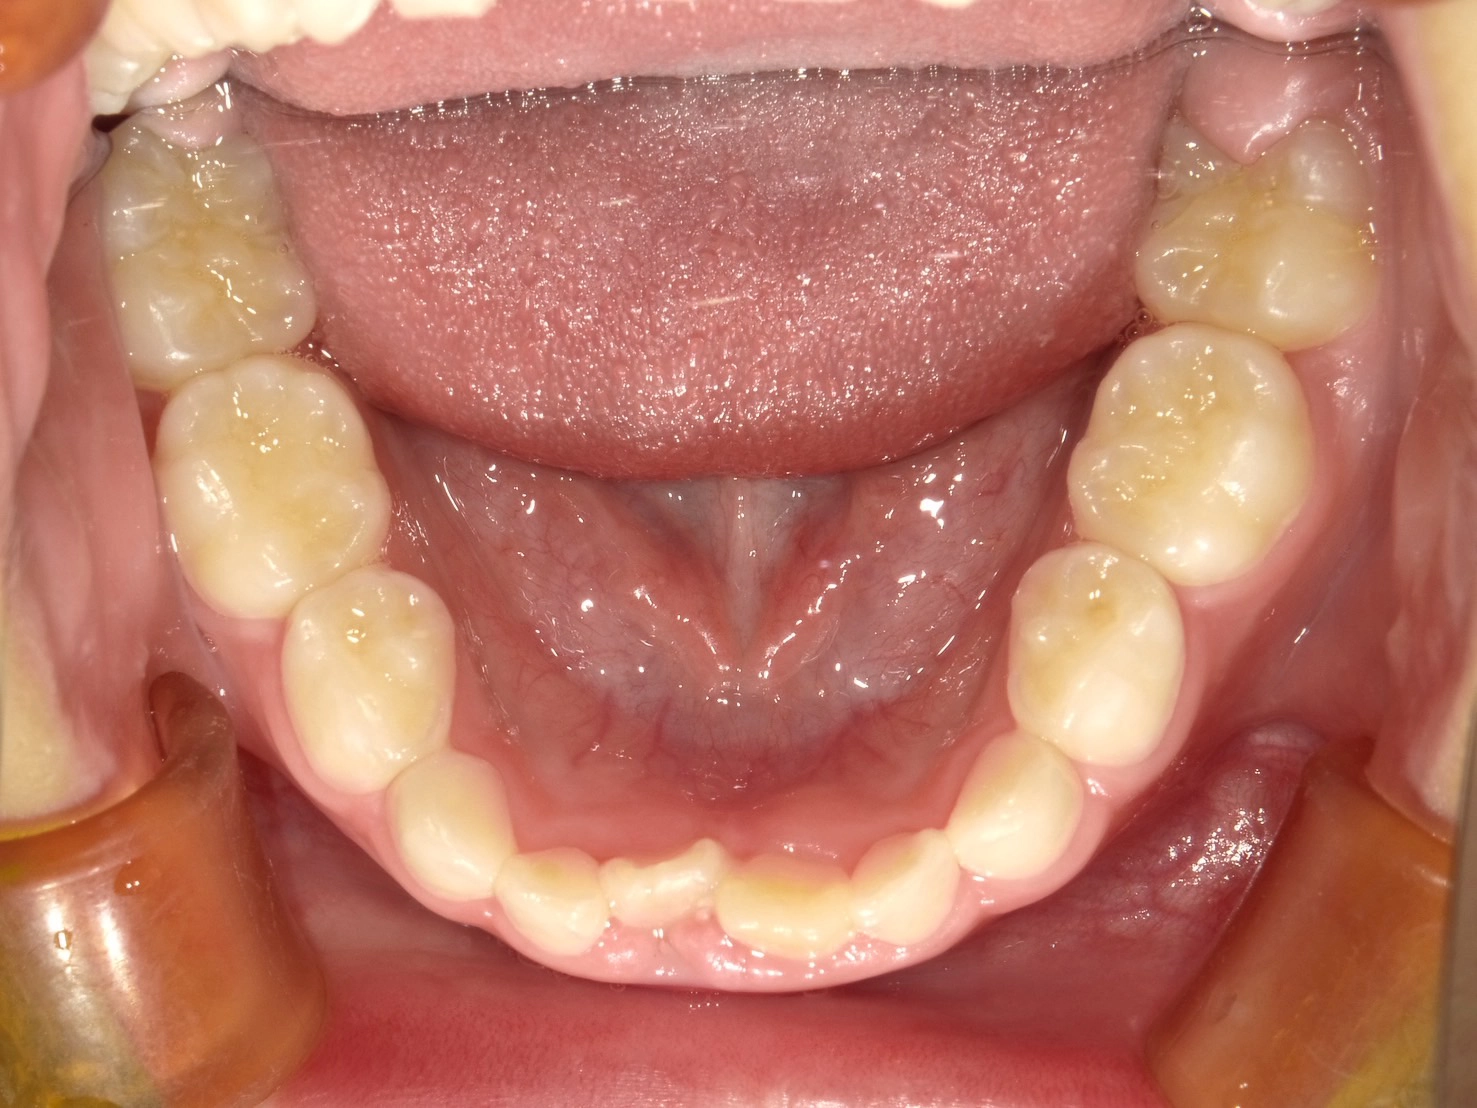

実際に小野歯科医院で行っているマイオブレースを用いた小児矯正の症例を紹介します。

どんどんきれいな歯並びになっていく様子を一緒に確認していきましょう!

治療前

年齢 | 6歳 |

性別 | 男性 |

主訴 | 下の前歯のガタつきが気になる |

診断名 | 叢生 |

治療内容 | マイオブレース矯正 |

治療期間 | 治療開始2ヶ月時点での変化 |

2か月後